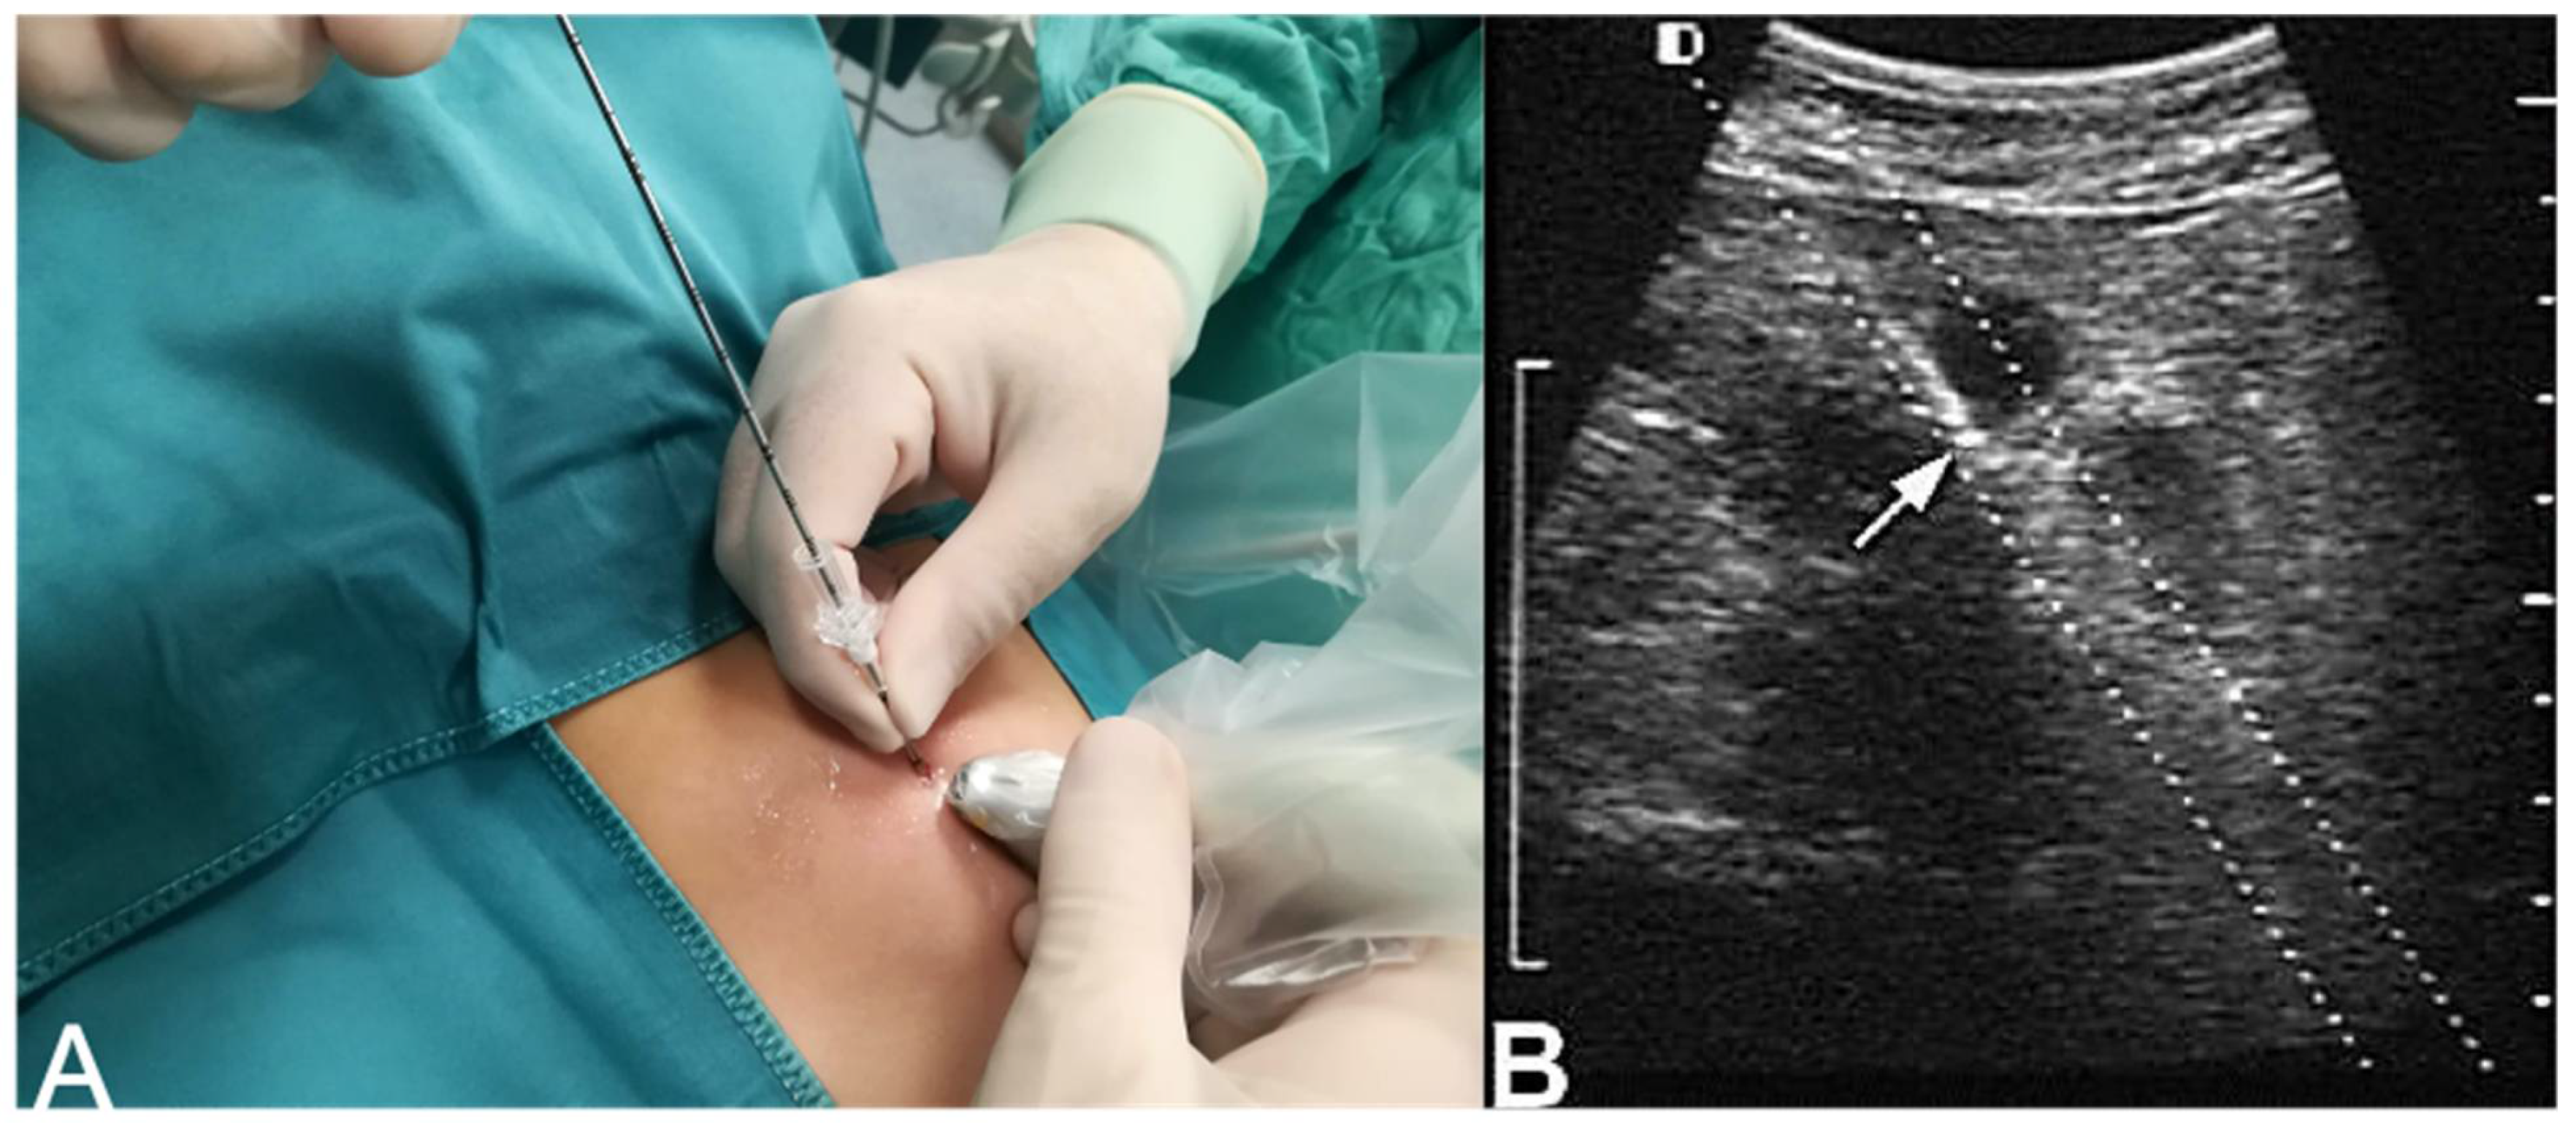

- Ultrasound-guided core needle biopsy

- 18 (37.5%) cases underwent an ultrasound-guided core needle biopsy, group (iii);